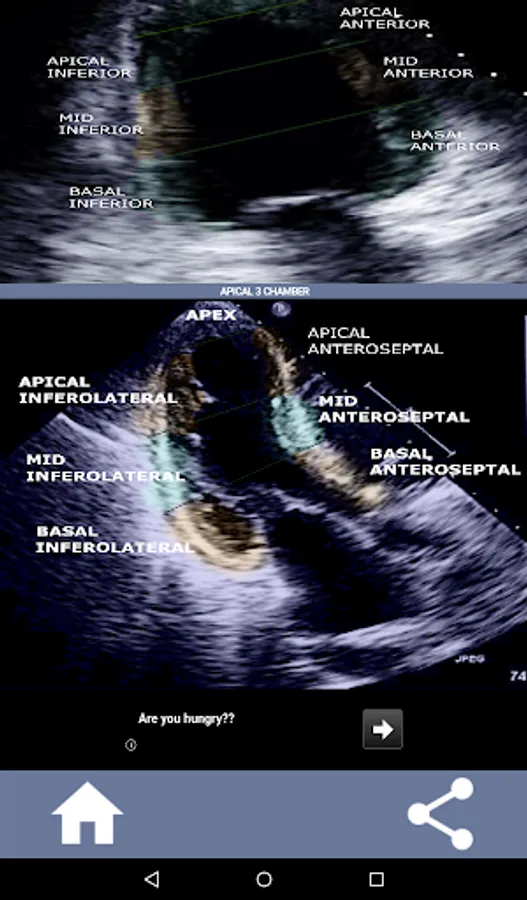

Understanding the AHA (American Heart Association) heart segments is of utmost importance for a cardiac sonographer to effectively communicate with the cardiologist who writes the report. By knowing the specific anatomical regions and their corresponding segments, the sonographer can accurately describe and communicate any abnormalities or findings, ensuring clear and concise communication between both professionals.

This understanding becomes particularly crucial when the cardiologist seeks to ascertain the precise location of a problem or when the on-call physician identifies an issue within a specific region, prompting the sonographer to accurately display the corresponding segment, such as the mid-inferior wall. Thus, possessing a comprehensive grasp of the AHA heart segments is essential skill set.

This app will test your knowlegde using actual echo images, which I often find to be the best teaching method.